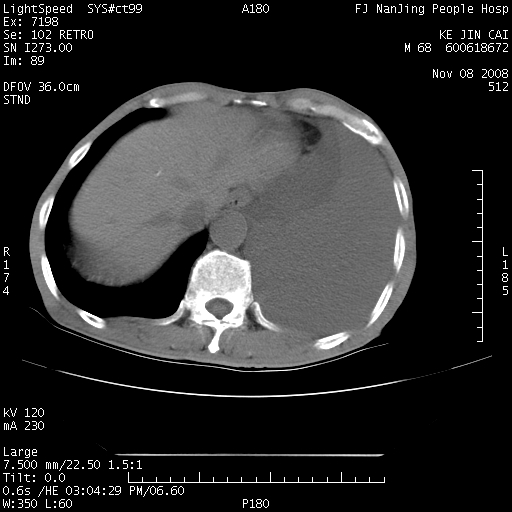

是个很有看头的病例,咋人气那么不旺?没多少人兴趣呢?这个病例几大怪:1   恶性肿瘤侵犯心肌左房怪,心肌一般不会被恶性肿瘤侵犯吧?2   左下肺均匀实变怪,内无含气,有别一般不张实变,含气肺泡完全为液体取代,而非一般不张实变的肺萎陷,冷不丁还以为是肿大的脾脏3   肿瘤本身怪,像tb肺不张4   这么有看头的病例没人气怪。呵呵。

左肺恶性肿瘤侵犯肺动脉,左心房内瘤栓,胸膜转移。